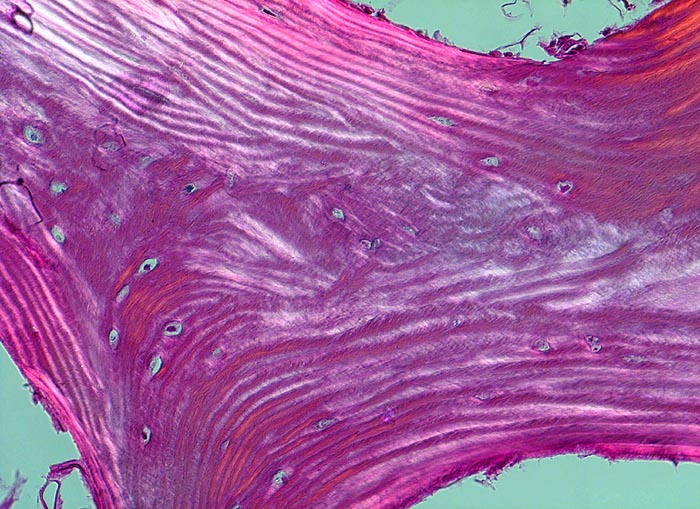

Normale Spongiosa

Knochen, Tibia

In der Doppelbrechung werden die regelmässig angeordneten Lamellen dieses Spongiosabälkchens besonders gut sichtbar.

Histologie

200